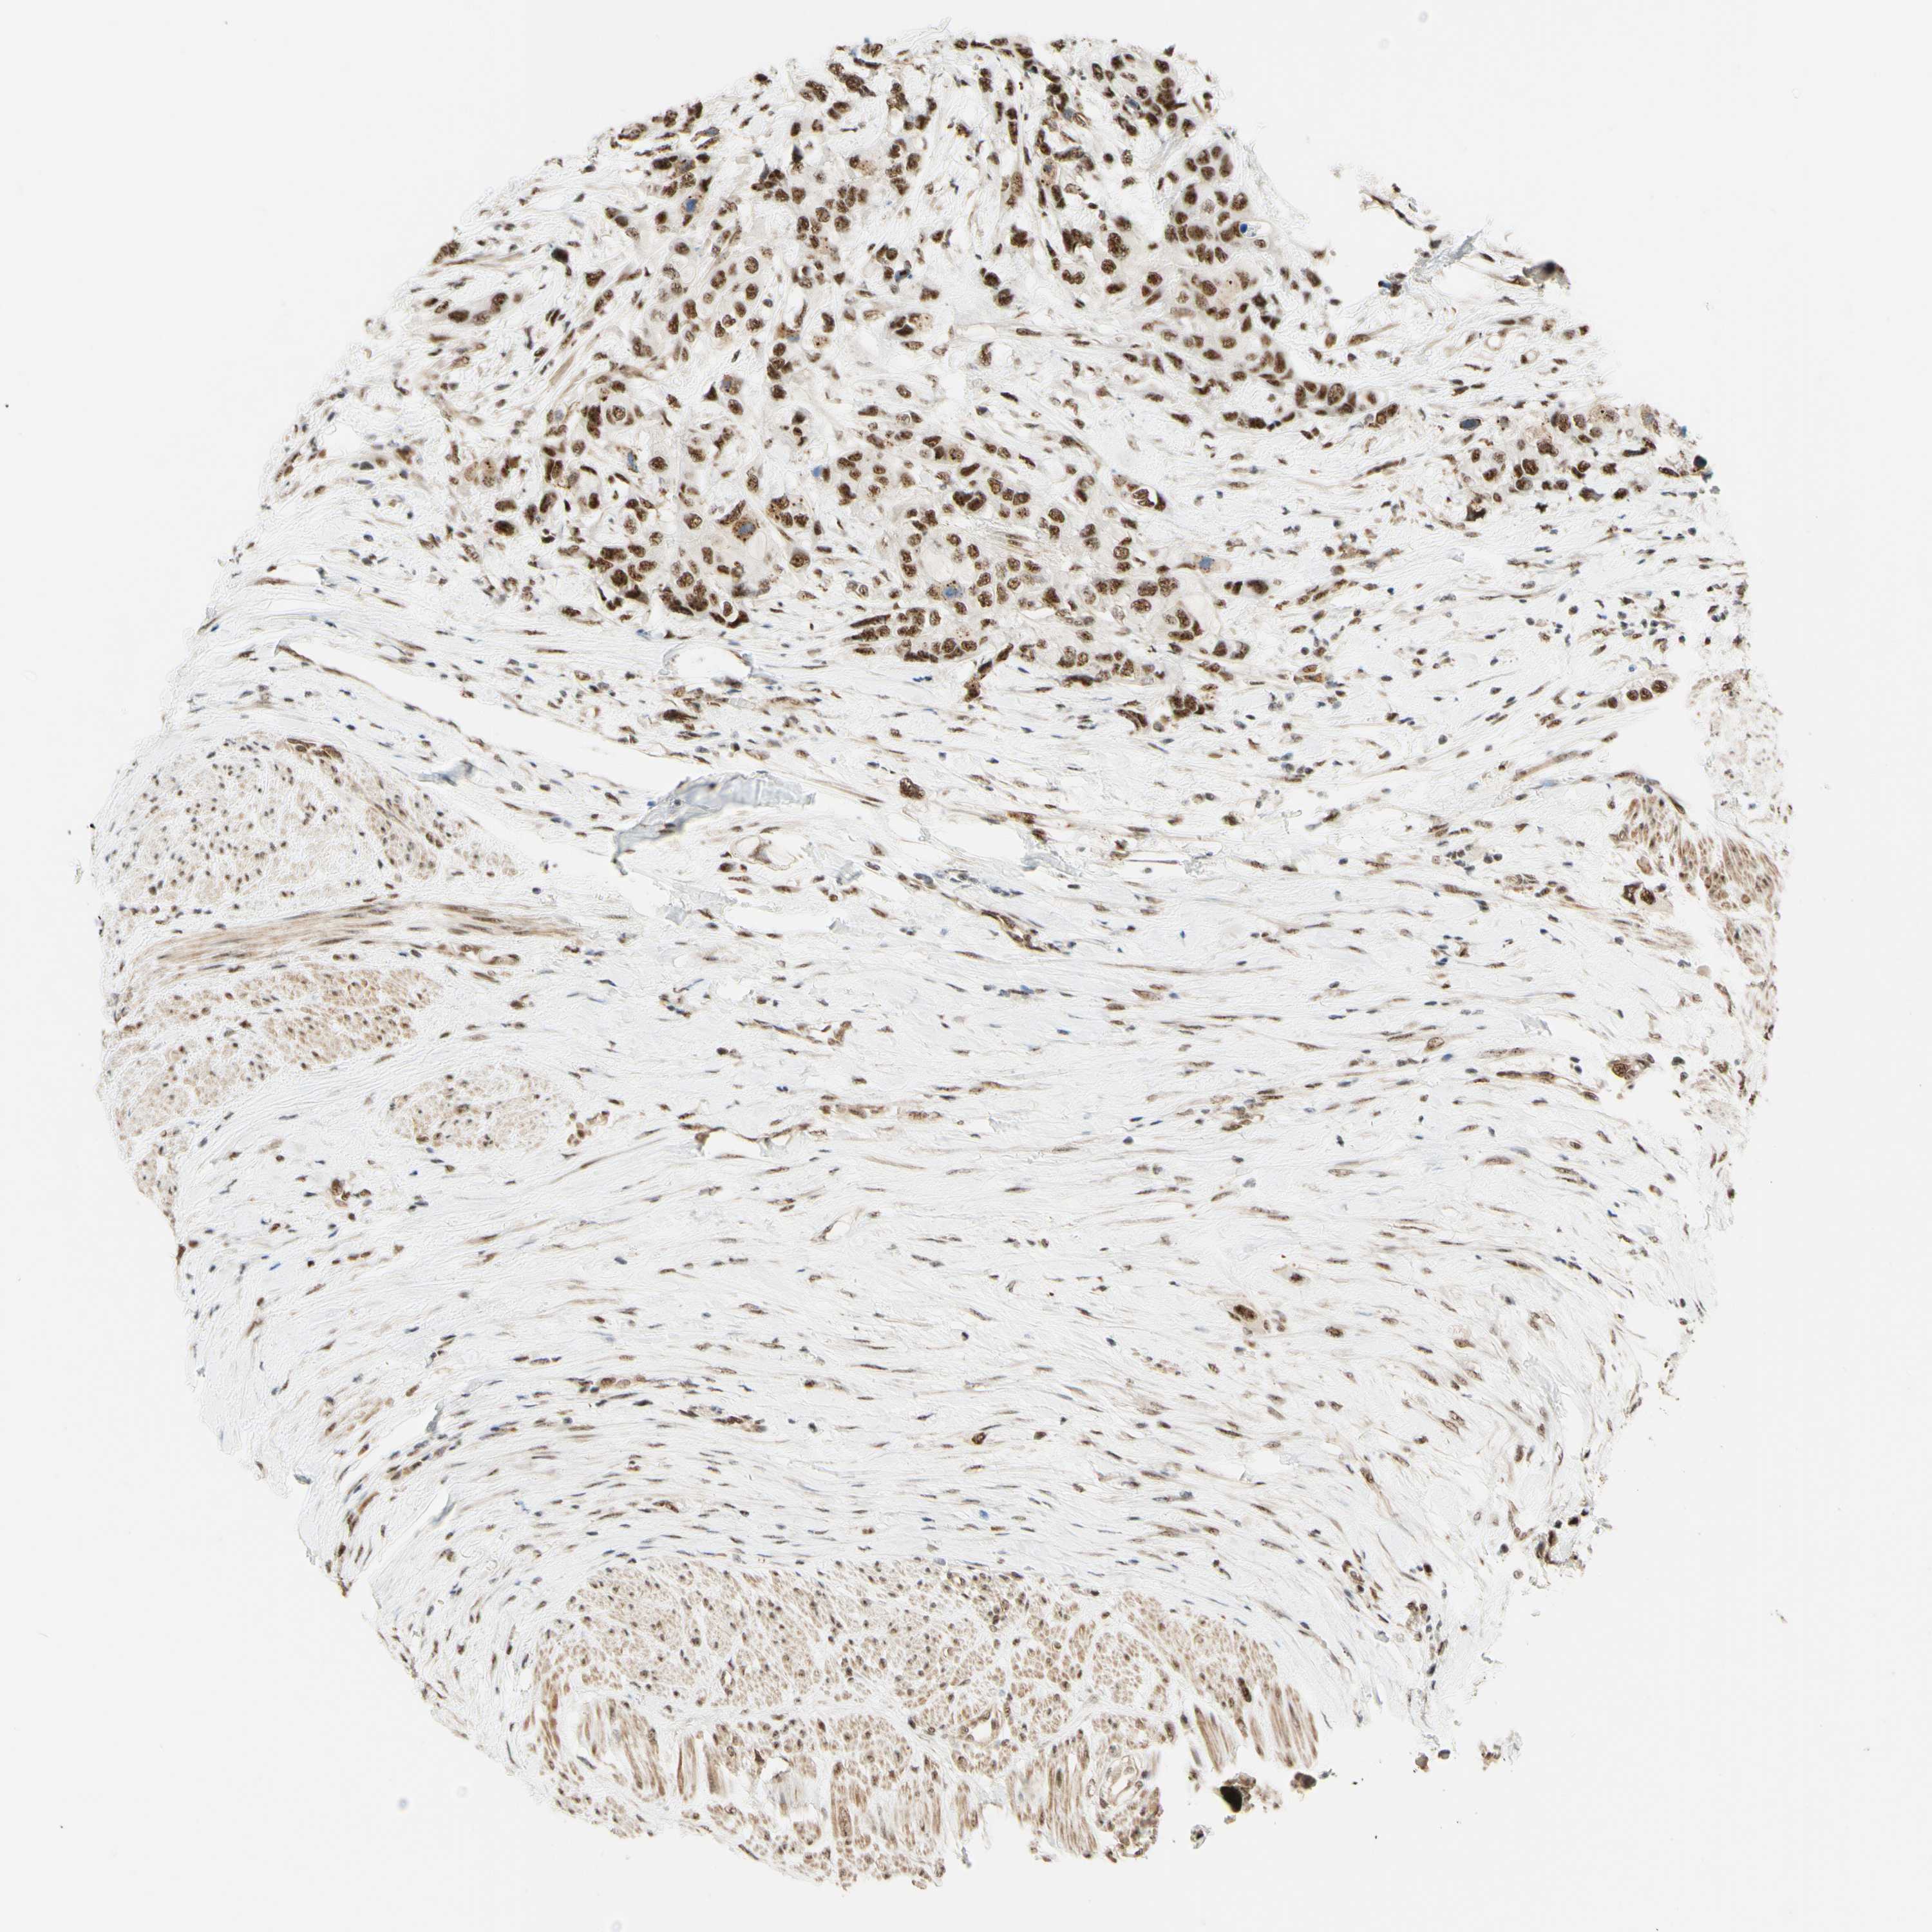

UROTHELIAL CANCER - Protein expressioni

A mouse-over function shows sample information and annotation data. Click on an image to view it in a full screen mode. Samples can be filtered based on level of antibody staining by selecting one or several of the following categories: high, medium, low and not detected. The assay and annotation is described here.

Antibody stainingi

Antibody staining in the annotated cell types in the current human tissue is reported as not detected, low, medium, or high, based on conventional immunohistochemistry profiling in selected tissues. This score is based on the combination of the staining intensity and fraction of stained cells.

Each image is clickable and will lead to virtual microscopy that enables deeper exploration of all samples and also displays staining intensity scores, fraction scores and subcellular localization as well as patient and tissue information for each sample.

Antibody HPA011352

Antibody CAB012273

Staining

High

Medium

Low

Not detected

Intensity

Strong

Moderate

Weak

Negative

Quantity

>75%

75%-25%

<25%

None

Location

Nuclear

Cytoplasmic/membranous

Cytoplasmic/membranous,nuclear

Urothelial carcinoma, Low grade

Urothelial carcinoma, High grade